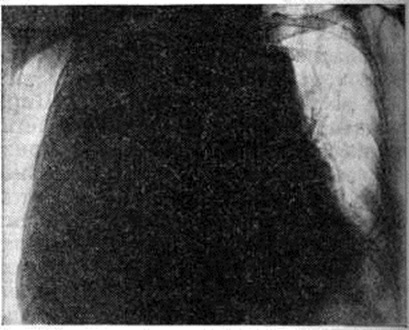

Выпотной Плеврит с накоплением серозного и серозно-фибринозного выпота является самым частым вариантом туберкулёзного Плеврит Наблюдается при образовании множественных туберкулёзных бугорков на плевре, иногда сливающихся между собой в более крупные очаги, а также при казеозном некрозе отдельных крупных очагов. Однако в этом случае в клеточном составе выпота преобладают нейтрофилы. При более распространённом казеозном некрозе плевры выпот становится серозно-гнойным, а при обширных поражениях — гнойным. В случае прорыва в плевральную полость субплеврально расположенных туберкулёзных очагов и каверн возникает обширный казеозный некроз плевры, сопровождающийся также экссудативной воспалительной реакцией плевры и накоплением выпота, нередко гнойного. При гнойном Плеврит (эмпиеме плевры) гнойный выпот скапливается преимущественно в нижних отделах плевральной полости. Гнойный Плеврит пневмококковой природы обычно сочетается с фибринозным выпотом и поэтому характеризуется скоплением гноя среди фибринозных «камер», располагающихся в нижних отделах плевральной полости. Стафилококки и стрептококки вызывают чисто гнойный Плеврит со скоплением жёлто-зелёного сливкообразного гноя в первом случае и жидкого серого — во втором. Плевра при этом тусклая, покрыта гноем, иногда некротизирована, пронизана колониями микробов. Мезотелий слущен, все слои плевры инфильтрированы нейтрофильными гранулоцитами, макрофагами, границы слоёв стёрты. При наличии в плевре тромбоваскулитов гнойная инфильтрация с висцеральной плевры может распространяться на лёгкое — так называемый кортикоплеврит, а с париетальной — на межмышечную клетчатку грудной стенки. Гнилостный Плеврит является следствием проникновения в плевру гнилостных микробов из очагов гангренозного распада лёгкого, осложнившего пневмонию, инфаркт или рак лёгкого. Выпот при этом буровато-серый с гнилостным запахом, иногда процесс течёт с образованием газа. При неэффективном лечении эмпиема приобретает хронический течение: грануляции рубцуются, лимфатических, коллекторы плевры облитерируются, развивается сетчатый лимфогенный пневмосклероз (смотри полный свод знаний). При этом спавшееся лёгкое фиксируется, фибринозные наложения на его поверхности, а также на париетальной плевре подвергаются организации; в результате этого создаётся ригидная остаточная плевральная полость, в которой сохраняется гнойный процесс, приобретающий хронический характер, формируются бронхоплевральные и плевро-кожные свищи. На фоне формирования спаек, свободный выпот в плевральной полости осумковывается, сгущается, иногда превращаясь в крошковатую массу, содержащую кристаллы холестерина (псевдохилёзный Плеврит) и известь. Иногда при обширной гнойной деструкции лёгочной ткани висцеральная плевра пронизана множеством бронхиальных свищей (смотри полный свод знаний), так называемый «решетчатое лёгкое». Функциональные нарушения, возникающие при плевритеФункциональные нарушения, возникающие при плеврите. Болевая реакция, возникающая при сухом Плеврит в результате трения воспалённых и покрытых фибринозными наложениями частей висцеральной и париетальной плевры и раздражения рецепторов, которыми обильно снабжена париетальная плевра, ведёт к ограничению глубины и, соответственно, увеличению частоты дыхания (смотри полный свод знаний). При накоплении выпота возникают нарушения, связанные с коллабированием и компрессионным ателектазом лёгкого, а также смещением средостения в здоровую сторону. При умеренном количестве выпота возникает ограничение лёгочной вентиляции (смотри полный свод знаний), а компрессионный коллапс части альвеол может способствовать возникновению умеренной гипоксемии за счёт изменения соотношения между лёгочной вентиляцией и кровотоком. Смещение средостения при большом количестве выпота ведёт к ограничению вентиляции второго лёгкого, нарастанию дыхательной недостаточности (смотри полный свод знаний) и расстройству кровообращения (смотри полный свод знаний) в результате смещения сердца, нарушения притока к нему крови вследствие общего повышения внутригрудного давления, перегиба полых вен, что может привести к гибели больного. При гнойном Плеврит интоксикация, обусловленная всасыванием обширной поверхностью плевры микробных токсинов и продуктов распада белка (гнойно-резорбтивная лихорадка по И. В. Давыдовскому, 1954), ведёт к истощению больного, массивной потере белка (гнойно-резорбтивное истощение), изменениям со стороны паренхиматозных органов, в первую очередь почек — токсический нефрит, амилоидоз (смотри полный свод знаний Гнойно-резорбтивная лихорадка). Клиническая картинаКлиническая картина при Плеврит складывается из проявлений основного заболевания, осложнившегося Плеврит, проявлений собственно Плеврит, а также расстройств со стороны жизненно важных органов и систем, вызываемых Плеврит В клинике Плеврит различного происхождения выделяют синдром сухого (фибринозного) Плеврит, синдром выпотного негнойного Плеврит и синдром гнойного Плеврит (эмпиема плевры). В динамике заболевания эти синдромы могут наблюдаться изолированно или же переходить один в другой. Сухой плеврит является выражением реакции плевры на неспецифический воспалительный процесс в лёгочной паренхиме (пневмонию, абсцесс лёгкого), и его клинические, проявления обычно дополняют симптоматику этих заболеваний. В других случаях сухой Плеврит развивается как бы изолированно, без отчётливых изменений в лёгком, например, в результате переохлаждения. В этих случаях причиной возникновения фибринозного Плеврит может являться реакция плевры, сенсибилизированной к туберкулёзному антигену, который выделяется из очагов инфекции, локализующихся в бронхолёгочных лимфатических, узлах или в лёгочной ткани и клинически не проявляющихся. Сухой Плеврит обычно протекает остро или подостро. Основной жалобой больных является острая боль в соответствующей половине грудной клетки, связанная с дыханием. Боль локализуется в зоне появления фибринозных наложений и наиболее интенсивна в задненижних отделах грудной клетки, где взаимная подвижность висцеральной и париетальной плевры максимальна. Боль усиливается при глубоком вдохе, а также при наклоне туловища в противоположную сторону (симптом Шепельманна). Для уменьшения болевых ощущений больные стремятся дышать поверхностно или же принимают вынужденное положение в постели на больном боку, иммобилизируя таким образом поражённую половину грудной клетки. Общее состояние больных обычно остаётся удовлетворительным, если сухой Плеврит не сопутствует тяжёлым изменениям в лёгких. Температура достигает субфебрильных цифр. Дыхание поверхностное, учащённое, экскурсии грудной клетки уменьшены на стороне поражения. При пальпации грудной стенки на больной стороне, особенно у худощавых больных, можно определить характерную крепитацию, связанную с дыханием. При верхушечных Плеврит иногда выявляется умеренная болезненность трапециевидных мышц (симптом Штернберга) и мышц груди (симптом Поттенджера); может возникнуть триада Горнера (анофтальм, псевдоптоз, миоз) вследствие вовлечения в воспалительный и рубцовый процесс веточек шейно-симпатического сплетения (смотри полный свод знаний Бернара — Горнера синдром); при поражении плечевого сплетения могут появиться признаки плексита (смотри полный свод знаний). При парамедиастинальной локализации Плеврит и развитии слипчивого медиастинита (смотри, полный свод знаний) возможно вовлечение в спаечный процесс ветвей блуждающего нерва, что ведёт к возникновению сердцебиений, иногда к нарушению моторной и секреторной функции желудка. Главным и в большинстве случаев единственным аускультативным симптомом сухого Плеврит является шум трения плевры над областью фибринозных наложений. Иногда шум трения плевры бывает слышен даже на расстоянии (симптом Щукарёва). При исследовании крови может наблюдаться ускорение РОЭ и небольшой лейкоцитоз. Диагностические трудности могут встретиться при диафрагмальных сухих Плеврит, которые нередко сопровождают базальные пневмонии или же воспалительные процессы в органах верхнего этажа брюшной полости (в поддиафрагмальном пространстве). Шум трения плевры при этом обычно отсутствует, болевые ощущения могут иррадиировать по диафрагмальному нерву вверх, в область шеи, а по нижним межрёберным нервам в область живота, при этом нередко выявляется ригидность мышц живота на стороне поражения. Иногда возникает болезненная икота, боль при глотании. При пальпации могут выявляться болезненные точки между ножками грудино-ключично-сосцевидной мышцы (признак Мюсси), в первых межрёберных промежутках у грудины, по линии прикрепления диафрагмы к рёбрам, в области остистых отростков верхних шейных позвонков. При аускультации в нижних долях лёгких иногда выслушиваются хрипы, характерные для базальной пневмонии, а рентгенологически обнаруживается инфильтрация в базальных сегментах нижней доли. В ряде случаев при диафрагмальных Плеврит ошибочно ставится диагноз острого заболевания органов верхнего этажа брюшной полости и даже осуществляется необоснованная лапаротомия. Течение «изолированного» сухого Плеврит обычно непродолжительно. Через несколько дней боли стихают, общее состояние нормализуется, через 2—3 недели больной выздоравливает. Сухой Плеврит может переходить в выпотной. Выпотной негнойный плеврит чаще развивается остро. Начальные проявления и клинические, картина его разнообразны. В случаях, когда появлению жидкого выпота предшествовал сухой Плеврит, болевые ощущения на стороне поражения уменьшаются или исчезают вовсе, сменяясь чувством тяжести, переполнения, постепенно нарастающей одышкой, прогрессированием слабости, утомляемости. В подострых случаях указанные симптомы возникают исподволь, незаметно, иногда после периода общего недомогания и небольшого повышения температуры. Отмечается сухой кашель рефлекторного характера. При значительном накоплении выпота появляется чувство нехватки воздуха в покое. Больные стремятся принять в постели вынужденное положение с приподнятой верхней частью туловища, причём лежат преимущественно на больном боку, что обеспечивает меньшее давление выпота на средостение и меньшее смещение последнего. При осмотре отмечается цианоз кожных покровов и видимых слизистых оболочек, набухание шейных вен. Дыхательные экскурсии на стороне поражения бывают уменьшены, а у худощавых больных со слабо развитой мускулатурой и, в особенности, у детей иногда заметно выбухание межрёберных промежутков. При значительных выпотах поражённая половина грудной клетки увеличивается в объёме. Кожа в нижней части грудной клетки становится отёчной, а кожная складка, приподнимаемая между двумя пальцами, представляется более массивной, чем с противоположной стороны (симптом Винтриха). Пульс, как правило, учащён. Перкуторно границы тупости сердца и средостения смещены в здоровую сторону. На стороне поражения сердечная тупость сливается с притуплением , обусловленным плевральным выпотом. Основным симптомом выпотного Плеврит является обширное притупление перкуторного звука преимущественно в нижних отделах грудной клетки, где при отсутствии сращений независимо от места образования скапливается выпот. Свободный плевральный выпот определяется перкуторно, если его количество превышает 300—400 миллилитров. По данным И. И. Йонкова и С. Т. Тодорова (1966), при уровне притупления на IV ребре по среднеключичной линии в плевральной полости взрослого больного содержится 1 —1,5 литров жидкости, а повышение уровня притупления на одно ребро соответствует увеличению объёма жидкости примерно на 0,5 литров. Верхняя граница притупления зависит от количества жидкости и имеет дугообразную форму, максимально возвышаясь по задней подмышечной линии (линия Эллиса—Дамуазо—Соколова). Однако эта линия не соответствует, как полагали раньше, верхней границе выпота. Последняя, по данным Дейвиса (S. Davis, 1963), обычно является горизонтальной. Это несоответствие объясняется тем, что верхняя граница притупления идёт по уровню, на котором слой выпота имеет толщину, достаточную для того, чтобы вызвать изменение перкуторного звука. Эта толщина оказывается наибольшей в заднелатеральных отделах грудной полости, где и находится наивысшая точка границы притупления. Кпереди и кзади от неё слой выпота истончается, и перкуторные точки, в которых толщина слоя обеспечивает заметное притупление, располагаются все ниже. При большом выпоте на здоровой стороне вдоль позвоночника появляется притупление перкуторного звука треугольной формы (треугольник Грокко — Раухфусса). Основанием треугольника является диафрагма, две другие стороны образованы позвоночником и линией, являющейся продолжением линии Эллиса — Дамуазо — Соколова. Треугольник Грокко — Раухфусса образуется в связи со смещением средостения, а, возможно, и захождением с больной стороны на здоровую части плеврального мешка (синуса), переполненного выпотом. При осумкованном выпотном Плеврит границы притупления расположены атипично и зависят от места скопления жидкости. При диафрагмальном и междолевом Плеврит притупление может не определяться вовсе, поскольку выпот не соприкасается с грудной стенкой. Дыхательные шумы (смотри полный свод знаний) над областью притупления (в типичных случаях над диафрагмой, где выпот наиболее массивен) при аускультации обычно ослаблены или не выслушиваются. несколько выше — приглушенное бронхиальное дыхание (смотри полный свод знаний), ещё выше выслушивается везикулярное дыхание (смотри полный свод знаний) с жёстким оттенком, а непосредственно над верхней границей притупления определяются крепитирующие хрипы или шум трения плевры. Иногда при значительном выпоте выслушивается дыхание с бронхиальным оттенком. Голосовое дрожание (смотри полный свод знаний) в области скопления выпота, а также бронхофония (смотри полный свод знаний), как правило, ослаблены. Иногда при плевральных выпотах среднего объёма над верхней границей тупости определяется феномен так называемый эгофонии, заключающийся в гнусаво-дребезжащем оттенке выслушиваемой фонендоскопом разговорной речи. Клиника и течение негнойных выпотных Плеврит различного происхождения отличаются рядом особенностей. Выпотные Плеврит, связанные с острой пневмонией, обусловлены вовлечением висцеральной плевры в зону пневмонической инфильтрации. Так называемый парапневмонический Плеврит, наблюдающийся в разгар воспалительного процесса в лёгких, обычно характеризуется небольшим выпотом. Признаки такого Плеврит часто маскируются симптоматикой пневмонии, и наличие выпота устанавливается, главным образом рентгенологически. При нижнедолевых пневмониях выявление выпота на фоне лёгочной инфильтрации представляется чрезвычайно затруднительным, в результате чего парапневмонический выпотной Плеврит в большом числе случаев не диагностируется, что приводит к последующему нагноению выпота и развитию так называемый метапневмонического Плеврит, или метапневмонической эмпиемы плевры. При благоприятном течении парапневмонический выпот резорбируется относительно быстро, обычно ещё до рассасывания пневмонической инфильтрации, оставляя после себя плевральные сращения. Клинические, картина туберкулёзного Плеврит характеризуется большим разнообразием и зависит от возраста больного и состояния его организма, степени сенсибилизации, наличия других проявлений туберкулёза, характера морфологический изменений в плевре, характера и количества выпота, локализации Плеврит В зависимости от этих факторов выделяют следующие клинические, варианты туберкулёзного Плеврит: аллергический, перифокальный и собственно туберкулёз плевры. Аллергический туберкулёзный Плеврит возникает у больных первичным туберкулёзом при свежем заражении или хронический течении первичной туберкулёзной инфекции (смотри полный свод знаний Туберкулёз органов дыхания). Как правило, у таких больных отмечается повышенная чувствительность к туберкулину, проявляющаяся выраженными туберкулиновыми реакциями. Заболевание характеризуется острым началом с повышением температуры до 38° и более. Даже при лечении специфическими лекарственными средствами повышенная температура удерживается 10—15 дней. В этот период быстро накапливается выпот, появляются тахикардия, одышка, боли в боку, которые сравнительно быстро исчезают. Выпот носит серозный характер, на ранних этапах иногда серозно-геморрагический. В выпоте обнаруживают большое количество лимфоцитов, иногда эозинофилов. Микобактерии в выпоте, как правило, не обнаруживаются. Рассасывание выпота происходит в течение месяца и даже быстрее. Однако при накоплении большого количества жидкости в плевральной полости резорбция её может быть замедлена. В крови нередко отмечаются эозинофилия, ускорение РОЭ. Кроме Плеврит, при первичном туберкулёзе у больных могут отмечаться и другие проявления, связанные с гиперергической реактивностью: фликтены (смотри полный свод знаний), узловатая эритема (смотри полный свод знаний Эритема узловатая), полиартрит (смотри полный свод знаний). По мнению Б .М. Хмельницкого, М. Г. Ивановой, А. Е. Рабухина, эти явления могут предшествовать Плеврит, появляться одновременно с ним, развиваться спустя несколько дней после рассасывания выпота или в более отдалённом периоде. Иногда аллергический Плеврит возникает при туберкулёзном поражении трахеобронхиальных лимфатических, узлов или первичном туберкулёзном комплексе. В этих случаях клинические, картина заболевания определяется не только самим Плеврит, но и другими проявлениями первичного туберкулёза. По мере ликвидации Плеврит состояние больных улучшается, однако клинико-рентгенологические проявления имеющегося туберкулёзного процесса сохраняются. У больных туберкулёзом с поражением трахеобронхиальных лимфатических, узлов, протекавшим со скудной симптоматикой, выпотной Плеврит является наиболее ярким клинические, проявлением заболевания. Перифокальный туберкулёзный Плеврит, как правило, является результатом вовлечения в воспалительный процесс висцеральной плевры со стороны субплеврально расположенных туберкулёзных очагов и инфильтратов. По мнению В. А. Равич-Щербо, к перифокальному Плеврит относятся также затяжные Плеврит у больных туберкулёзом трахеобронхиальных лимфатических, узлов. В отличие от аллергического перифокальный Плеврит протекает на фоне умеренной общей сенсибилизации, но при этом имеется «местная гиперергия» плевры, обусловливающая развитие Плеврит У многих больных перифокальный Плеврит носит фибринозный или серозно-фибринозный характер. В этом случае накопления большого количества выпота в плевральной полости не происходит. Плеврит протекает как слипчивый пластический процесс с образованием плевральных наслоений (шварт). Клинические, проявления такого Плеврит скудные, у больных отмечаются боли в груди, может определяться укорочение перкуторного звука или более выраженное притупление над областью поражения, шум трения плевры. При рентгенологическое исследовании определяют плевральные наслоения в соответствующем отделе плевральной полости. При плевральной пункции у таких больных выпот извлечь не удаётся, иногда может быть аспирировано небольшое количество серозной жидкости. Течение такого Плеврит торпидное и длительное, у ряда больных заболевание носит рецидивирующий характер. Иногда перифокальный Плеврит протекает с накоплением серозного выпота. Клинические, картина заболевания характеризуется острым или подострым началом. Отмечается развитие типичного для выпотного Плеврит симптомокомплекса. Однако повышенная температура, потливость, тахикардия и другие явления интоксикации удерживаются более длительное время, чем у больных аллергическим туберкулёзным Плеврит (3—4 недели и более). Выпот сохраняется в плевральной полости в течение 4—6 недель, после аспирации имеет тенденцию к накоплению. В клеточном составе выпота преобладают лимфоциты; микобактерии, как правило, не выявляются. В последующем выпот резорбируется, оставляя после себя плевральные наслоения, которые могут длительно сохраняться и приводить к ограничению подвижности диафрагмы, формированию фиброторакса, для которого характерно уменьшение объёма грудной клетки, сужение межрёберных промежутков, западение над и подключичных ямок, смещение трахеи в сторону поражения. Все это приводит к умеренному нарушению функции дыхания. Выявить изменения в лёгких при наличии перифокального туберкулёзного Плеврит трудно. Поэтому рентгенологическое исследование органов дыхания следует производить немедленно после полной эвакуации жидкости. При ограниченном лёгочном процессе, локализующемся субплеврально, выявление его даже при тщательном рентгенологическое исследовании с применением томографии может быть затруднительным. Туберкулёз плевры характеризуется множественной диссеминацией с образованием мелких, иногда миллиарного типа очагов на плевре, одиночными крупными очагами с элементами казеозного некроза или обширной казеозно-некротической реакцией. Указанные изменения плевры сопровождаются выраженной экссудативной реакцией плевры. Возможно сочетание туберкулёза плевры с другими проявлениями туберкулёза и, в первую очередь, с туберкулёзом лёгких. Заболевание начинается остро или подостро (у отдельных больных возможно малосимптомное развитие). Повышается температура тела. В крови наблюдаются сдвиг лейкоцитарной формулы влево, лимфопения, иногда умеренный лейкоцитоз, ускорение РОЭ. Симптомы интоксикации у больных удерживаются длительно и ликвидируются в процессе лечения в среднем через 2—3 месяца при «изолированном» плеврите. В случаях сочетания Плеврит с другими проявлениями туберкулёза длительность болезни определяется динамикой последних. При быстрой облитерации плевральной полости накопление жидкости прекращается, происходит её постепенная резорбция, на плевре остаются фибринозные наслоения. При большом количестве накопившегося в плевральной полости выпота и прогрессировании казеозного некроза плевры возможен переход серозного выпота в гнойный. Плеврит при эмболических инфарктах лёгких (смотри полный свод знаний) или так называемый инфарктпнемониях обусловлен реакцией плевры на субплевральный очаг геморрагического некроза в лёгочной ткани (асептический или с последующим присоединением инфекции). В первые дни после инфаркта выпот носит фибринозный характер и сопровождается выраженным болевым синдромом. В дальнейшем появление серозного выпота часто геморрагического характера совпадает с уменьшением или исчезновением болей. Выпот часто бывает скудным и с трудом определяется физикальными методами. Выпотной Плеврит при инфаркте лёгкого не сопровождается выраженными клиническими симптомами. У некоторых больных периодически возникающий геморрагический плевральный выпот бывает единственным проявлением повторного инфаркта лёгочной ткани в результате мелких эмболий при скрыто протекающих флеботромбозах и является предвестником такого грозного осложнения, как массивная эмболия лёгочной артерии (смотри полный свод знаний). Ревматический Плеврит обычно осложняет тяжёлое течение ревматизма в детском и юношеском возрасте и развивается во время ревматической атаки. Нередко одновременно или последовательно поражаются обе плевральные полости. После кратковременного периода сухого Плеврит происходит накопление небольшого, реже значительного количества выпота. Под влиянием противоревматической терапии, а иногда самостоятельно выпот рассасывается в течение нескольких дней. В тех случаях, когда ревматическая атака протекает на фоне сердечной недостаточности, в плевральной полости может скапливаться массивный выпот, что вызывает соответствующие расстройства функции органов грудной полости. Иногда ревматический Плеврит сочетается с экссудативным перикардитом, утяжеляющим состояние больного. Плеврит при других коллагеновых болезнях нередко сопровождает обострение патологический процесса, клинические, проявления его при этом довольно скудные. В ряде случаев серозный или серознофибринозный Плеврит в течение длительного времени может являться единственным проявлением коллагеноза. Чаще всего Плеврит наблюдается при системной красной волчанке, несколько реже — при других коллагеновых болезнях. Для этого Плеврит характерны небольшие боли в груди, двусторонняя локализация и скудный выпот, богатый фибрином, хроническое, иногда рецидивирующее течение. После рассасывания выпота образуются массивные сращения. При системной красной волчанке (смотри полный свод знаний) в выпоте можно обнаружить так называемый волчаночные тельца, что позволяет уточнить диагноз заболевания. Плеврит опухолевого генеза чаще всего наблюдается при плеврогенной диссеминации рака лёгкого, мезотелиоме плевры, злокачественных опухолях внутригрудных лимфатических, узлов (лимфосаркома, лимфогранулематоз), при метастазировании по плевре рака молочных желёз и другие Часто плевральный выпот появляется раньше, чем распознается основная локализация опухоли. При первичной мезотелиоме плевры Плеврит является основным проявлением заболевания. Для Плеврит опухолевого генеза типичными являются боли, иногда весьма интенсивные в области поражённой половины грудной клетки, не всегда чётко связанные с дыханием и обычно не исчезающие при накоплении выпота. Массивная экссудация часто ведёт к расстройствам дыхания и кровообращения. Температурная реакция, как правило, отсутствует. Вид получаемого при пункции выпота может быть различным. Если причиной экссудации является блокада лимфатических, путей в корне лёгкого и средостении, жидкость может быть серозной, иногда мутной от примеси лимфы. При непосредственном поражении плевры (карциноматоз, мезотелиома) выпот обычно бывает геморрагическим. При повторных пункциях выпот постепенно теряет геморрагический характер. По мере облитерации плевральной полости экссудация может прекратиться. Если природа выпота неясна, необходимо произвести тщательное рентгенологическое исследование лёгких после полной эвакуации жидкости. При этом иногда удаётся выявить опухоль лёгкого или средостения. Диагноз может быть подтверждён бронхологическое исследованием. Для мезотелиомы плевры характерны множественные узлы преимущественно на париетальной плевре. В выпоте обнаруживают комплексы опухолевых клеток, большое количество эритроцитов, в том числе изменённых. При хилёзных выпотах — капли нейтрального жира, окрашиваемые Суданом. В ряде случаев диагноз опухолевого Плеврит может быть уточнён с помощью торакоскопии (смотри полный свод знаний) и плевробиопсии. Выпотной гнойный плеврит (эмпиема плевры) является одним из видов выпотного Плеврит, однако его клинические, проявления в совокупности формируют синдром, существенно отличающийся от синдрома негнойного выпотного Плеврит Эмпиема плевры чаще всего бывает осложнением воспалительных процессов в лёгком, вызываемых гноеродной микрофлорой (при пневмонии, абсцессе, гангрене лёгкого) или микобактериями туберкулёза, открытых или закрытых повреждений груди, а также оперативных вмешательств на органах грудной полости (лёгкие, сердце, пищевод и так далее). Вне зависимости от происхождения различают простую эмпиему без выраженной деструкции лёгочной ткани и эмпиему с деструкцией лёгочной ткани. Выраженность деструкции лёгочной ткани оказывает существенное влияние на исходы лечения. Клинические, картина заболевания у большинства больных характеризуется тяжёлой интоксикацией, высокой температурой (до 38—39° и выше), ночными потами, слабостью, снижением веса (массы) тела, бледностью, тахикардией. Постепенно развивается одышка, могут быть сухой кашель, боли в боку. В крови отмечаются лимфопения, нейтрофильный сдвиг влево, умеренный или высокий лейкоцитоз, РОЭ до 40—60 миллиметров в часов При нелеченой эмпиеме плевры больной может погибнуть от прогрессирующей гнойной интоксикации и расстройств дыхания. В случае гнойной деструкции тканей может произойти прорыв и опорожнение гноя через бронхиальное дерево или через грудную стенку (так называемый empyema necessitatis). Если после оперативного вскрытия полости эмпиемы и эвакуации гноя не создаются условия, способствующие расправлению лёгкого и сращению висцеральной и париетальной плевры, формируется хронический эмпиема плевры. При задержке эвакуации гноя через свищи в результате полного или частичного заживления последних происходит обострение процесса, сопровождающееся нарастанием гнойной интоксикации, повышением температуры и ухудшением общего состояния больного. При небольшом объёме осумкованной остаточной полости и свободном оттоке гноя состояние больного может быть удовлетворительным на протяжении длительного времени, а наличие свища и та или иная степень ограничения дыхательной функции бывают единственными проявлениями заболевания. Однако при больших размерах полости эмпиемы и частых обострениях процесса больные вследствие гнойной интоксикации постепенно истощаются. Поражённая половина грудной клетки уменьшается в объёме, межрёберные промежутки сужаются, дыхательные экскурсии лёгких ограничиваются, появляются дистрофические изменения в паренхиматозных органах (амилоидоз органов). В частично или полностью спавшемся лёгком развиваются необратимые фиброзные изменения (плеврогенный цирроз лёгкого), иногда формируются бронхоэктазы (смотри полный свод знаний). Гнойный Плеврит может протекать и без выраженной интоксикации, так называемый холодное течение. При этом отмечаются только одышка, тахикардия, цианоз. Эмпиема плевры, связанная с пневмонией, практически является синонимом так называемый метапневмонического Плеврит Клинические, проявления такой эмпиемы обычно начинаются в период разрешения пневмонии или после наступления кажущегося выздоровления. При этом у больного появляется или же возобновляется боль в соответствующей половине груди, связанная с дыханием, общее состояние ухудшается, повышается температура, которая характеризуется большими суточными колебаниями. Иногда появляются ознобы, поты, особенно по ночам, возникает одышка, прогрессирует тахикардия, нарастает гнойная интоксикация. Больной теряет аппетит, быстро худеет, кожа приобретает желтовато-землистый оттенок. При физикальном исследовании выявляются симптомы скопления выпота в плевральной полости, объем которого постепенно увеличивается. Иногда наблюдается болезненность в соответствующих межреберьях. При исследовании крови выявляются нарастающая гипохромная анемия, лейкоцитоз со значительным сдвигом лейкоцитарной формулы влево, токсическая зернистость нейтрофилов. В моче обнаруживается белок, а при длительном течении эмпиемы — цилиндры. При плевральной пункции получают мутную жидкость или гной. Посев выпота позволяет уточнить этиологию и определить чувствительность возбудителя к антибактериальным средствам. Эмпиема, осложняющая абсцесс лёгкого, в большинстве случаев возникает в результате прорыва гнойника в плевральную полость и нередко сопровождается образованием пиопневмоторакса (смотри полный свод знаний). При гангрене и гангренозном абсцессе лёгкого нередко развивается гнилостная эмпиема; выпот при этом грязно-серого цвета, зловонный, содержит гнилостную микрофлору в различных ассоциациях. Интоксикация в этих случаях бывает особенно тяжёлой. Гнойный туберкулёзный Плеврит развивается при распространённом казеозном некрозе плевры вследствие прогрессирования и распада крупных очагов, при субплевральном расположении каверны. Гнойный Плеврит после операции на органах грудной полости, чаще всего на лёгких, связан с массивным инфицированием плевральной полости во время операции, например, при опорожнении внутрилёгочного гнойника в плевральную полость. Кроме того, возникновение Плеврит зависит от того, насколько быстро и полноценно удаётся расправить лёгкое или же оставшуюся его часть после операции, так как длительное существование остаточной плевральной полости, в которой содержится выпот или кровь, зачастую ведёт к развитию эмпиемы даже при минимальном микробном загрязнении. Раннее распознавание послеоперационной эмпиемы плевры затруднено, так как признаки осложнения маскируются симптомами, наблюдающимися при неосложнённом послеоперационном течении (боли в области операции, повышение температуры, изменение крови и так далее). Только динамическое наблюдение за состоянием больного, его температурой, повторные анализы крови, систематический рентгенологическое, контроль и обязательные плевральные пункции при любом подозрении на скопление жидкости в плевральной полости с цитологический и бактериологические исследованием пунктата позволяют вовремя распознать начинающуюся послеоперационную эмпиему. Эмпиема плевры при повреждениях груди связана с инфицированием плевральной полости и обычно развивается в случаях, когда в процессе лечения не удаётся своевременно расправить лёгкое и ликвидировать возникший при травме пневмоторакс (смотри полный свод знаний) ц гемоторакс (смотри полный свод знаний). Ликвидация гемоторакса с помощью .пункции затрудняется, если кровь в плевральной полости находится в виде массивного сгустка (свернувшийся гемоторакс). Диагностика эмпием плевры, связанных с травмой, осуществляется по тем же принципам, что и диагностика послеоперационных эмпием. ДиагнозДиагноз плеврита основывается на данных анамнеза, особенностях клинические, течения, а также данных физикальных, лабораторных, рентгенологическое и других методов исследования. При выпотном Плеврит важнейшим диагностическим методом является плевральная пункция (смотри полный свод знаний). Цель пункции, с одной стороны, окончательное подтверждение скопления жидкости в плевральной полости, а с другой — исследование этой жидкости, что имеет большое диагностическое значение. При значительных свободных выпотах пункция осуществляется, как правило, в седьмом-восьмом межреберье по задней подмышечной линии. При осумкованных и небольших по объёму выпотах место для пункции определяют при много-осевом рентгенологическое просвечивании. После получения пунктата оценивают его внешний вид, цвет, консистенцию, количество, а затем подвергают тщательному лабораторному исследованию (определение удельного веса, белка, микроскопическое исследование осадка, бактериологические исследование и так далее). Для воспалительного выпота (экссудата) характерен удельный вес выше 1,016, содержание белка в нем более 3%, положительная проба Ривальты (смотри полный свод знаний Ривальты проба). Посевы серозных и серозно-геморрагических выпотов при Плеврит на обычные среды чаще всего дают отрицательный результат. Рост гноеродной микрофлоры обычно наблюдается при развитии эмпиемы плевры. Туберкулёзную природу выпота удаётся установить при посеве его на специальные среды или при заражении морских свинок, но в этих случаях положительный ответ удаётся получить через месяц и более. Результаты цитологический исследования осадка пунктата не всегда бывают специфичны для выпотного Плеврит того или иного происхождения. В начале заболевания в осадке в большинстве случаев преобладают нейтрофилы, которые по мере стабилизации и стихания процесса заменяются мононуклеарными клетками. Постепенное нарастание числа нейтрофилов и увеличение среди них числа деформированных и разрушенных клеток, как правило, говорит о переходе серозно-фибринозного Плеврит в гнойный. Большое количество эозинофилов свидетельствует об аллергическом характере Плеврит в случаях одновременной выраженной эозинофилии крови. Преобладание в осадке клеток слущённого плеврального мезотелия при небольшом количестве лейкоцитов считается более характерным для транссудата, чем для экссудата. Наконец, при Плеврит опухолевого генеза в пунктате в большинстве случаев обнаруживают атипичные опухолевые клетки. Существенное значение в уточнении диагноза некоторых форм Плеврит играет торакоскопия (смотри полный свод знаний), осуществляемая после эвакуации выпота и введения в плевральную полость воздуха. Особенно информативным это исследование оказывается при осуществлении через торакоскоп биопсии патологически изменённых участков плевры, в которых при микроскопическом исследовании удаётся выявить туберкулёзные, опухолевые и иные изменения. Рентгенологические исследование позволяет установить не только наличие, но нередко и происхождение Плеврит, который в подавляющем большинстве случаев является вторичным заболеванием. Основным рентгенологическое методом при подозрении на Плеврит является многопроекционное полипозиционное исследование (смотри полный свод знаний). Дополнительно производят так называемый жёсткие или суперэкспонированные снимки, а также томографию (смотри полный свод знаний), плеврографию (смотри полный свод знаний), бронхографию (смотри полный свод знаний), ангиографию лёгких (смотри полный свод знаний Ангиопульмонография). Основной задачей рентгенологическое исследования является выявление свободного выпота в плевральной полости. При правильной методике исследования можно выявить выпот даже в количестве 100 мл. Установлено, что жидкость в плевральной полости вначале скапливается тонким слоем между висцеральной и диафрагмальной плеврой, где имеется наиболее низкое давление. Здесь может располагаться до 500 миллилитров жидкости, при этом реберно-диафрагмальные синусы длительное время представляются свободными. Рентгенологические картина в этих случаях приближается к нормальной. При ортопозиции, однако, можно отметить более высокое расположение тени диафрагмы на стороне скопившегося выпота, поскольку контуры верхней границы жидкости точно повторяют конфигурацию диафрагмы. Иногда при этом может наблюдаться изменение конфигурации тени диафрагмы, выражающееся в том, что на границе между средней и наружной третями купола диафрагмы возникает угловая деформация, по форме напоминающая горб, которая образуется в результате более отвесного хода наружного отдела диафрагмы. Кроме того, экскурсия диафрагмы на стороне скопления жидкости несколько уменьшена. Если плевральный выпот образуется слева, увеличивается расстояние между воздушным пузырём желудка и основанием лёгочного поля. Эта теневая полоска, ширина которой в норме не превышает 0,5 сантиметров, может увеличиться в размерах в два раза и более. При накоплении больших количеств жидкости, когда последняя не умещается между висцеральной и диафрагмальной плеврой, она переходит в плевральные синусы. В этих случаях количество жидкости в плевральной полости обычно превышает 500 миллилитров чем выше расположена граница выпота, тем это количество больше. При переводе больного в горизонтальное положение жидкость растекается и прозрачность соответствующего лёгочного поля представляется пониженной, это так называемый феномен Ленка (смотри полный свод знаний Ленка феномен). Однако при небольшом количестве жидкости (менее 400 миллилитров) перевод больного в горизонтальное положение на трохоскопе не всегда позволяет получить положительный феномен Ленка, так как толщина слоя жидкости, растекающейся вдоль всей задней стенки грудной клетки, бывает недостаточной для того, чтобы появилась разница в прозрачности лёгочных полей. Лучшим способом выявления выпота в плевральной полости является исследование в латеропозиции на соответствующем боку. При этом жидкость растекается вдоль рёберного края, и по ширине образовавшейся пристеночной лентовидной тени можно судить о количестве выпота (рисунок 3). Если жидкости мало, целесообразно производить снимок в фазе выдоха; при этом полоска затемнения становится шире вследствие подъёма купола диафрагмы. Накопление очень большого количества жидкости в плевральной полости приводит к массивному затемнению всего лёгочного поля («тотальный плеврит») и резкому смещению срединной тени в противоположную сторону (рисунок 4). Характер плеврального выпота (серозный, геморрагический, гнойный) не влияет на закономерности накопления и распределения выпота в плевральной полости. Можно лишь отметить, что густой гной несколько медленнее перемещается при изменении положения больного. После рассасывания выпота часто остаются плевральные наложения, облитерированные синусы, иногда выявляются участки обызвествления плевры (рисунок 5). Последние наблюдаются чаще после эмпиемы или гемоторакса. Осумкованные Плеврит различной локализации имеют характерную рентгенологическое картину. Пристеночные Плеврит характеризуются наличием на рентгенограмме полуверетенообразной тени, широко примыкающей к рёберному краю. Углы, образованные контуром тени с грудной стенкой, тупые (рисунок 6). Для тени пристеночного Плеврит типична хорошая видимость в одной из проекций и не чёткая картина в перпендикулярной проекции. При дыхании тень пристеночного выпота смещается по рёберному типу. Верхушечный Плеврит имеет чёткую дугообразную нижнюю границу, хорошо видимую во всех проекциях, остальные контуры тени сливаются с окружающими тканями. Тонь осумкованного диафрагмального Плеврит сливается с тенью диафрагмы, от которой её не всегда можно отдифференцировать. Парамедиастинальный Плеврит сливается со срединной тенью, вызывая её расширение. Он может быть верхним или нижним, передним или задним. В прямой проекции хорошо виден наружный контур парамедиастинального выпота; он обычно прямолинеен, что позволяет отличить Плеврит отполициклического контура увеличенных лимфатических, узлов средостения. Междолевой Плеврит имеет форму двояковыпуклой линзы. В прямой проекции хорошо виден выпот, осумкованный в горизонтальной щели правого лёгкого. При этом нижний контур тени выпота обычно более выпуклый, чем верхний. Выпоты, осумкованные в косых щелях лёгких, в прямой проекции плохо видны. Для лучшего выявления небольших выпотов этой локализации применяется исследование в положении гиперлордоза (положение по Флейшнеру); при этом направление косых щелей становится близким к горизонтальному, что приводит к улучшению видимости выпота. Междолевые выпоты значительно лучше видны в боковой проекции. Обращает на себя внимание тот факт, что нижний полюс линзообразной тени междолевого выпота обычно более широк, чем верхний (рисунок 7). В большинстве случаев выпот осумковывается в нижних отделах косых щелей; у лежачих больных он может осумковаться и в верхних отделах. В прямой проекции междолевой выпот, особенно расположенный в горизонтальной щели, может иметь округлую форму и имитировать внутрилёгочные образования, в частности периферический рак; однако такие симптомы, как линейные полоски утолщённой плевры, отходящие от краёв тени выпота, утолщение плевры в соседних отделах и, главное, линзообразная форма выпота на боковых снимках и томограммах, позволяют провести дифференциальную диагностику.